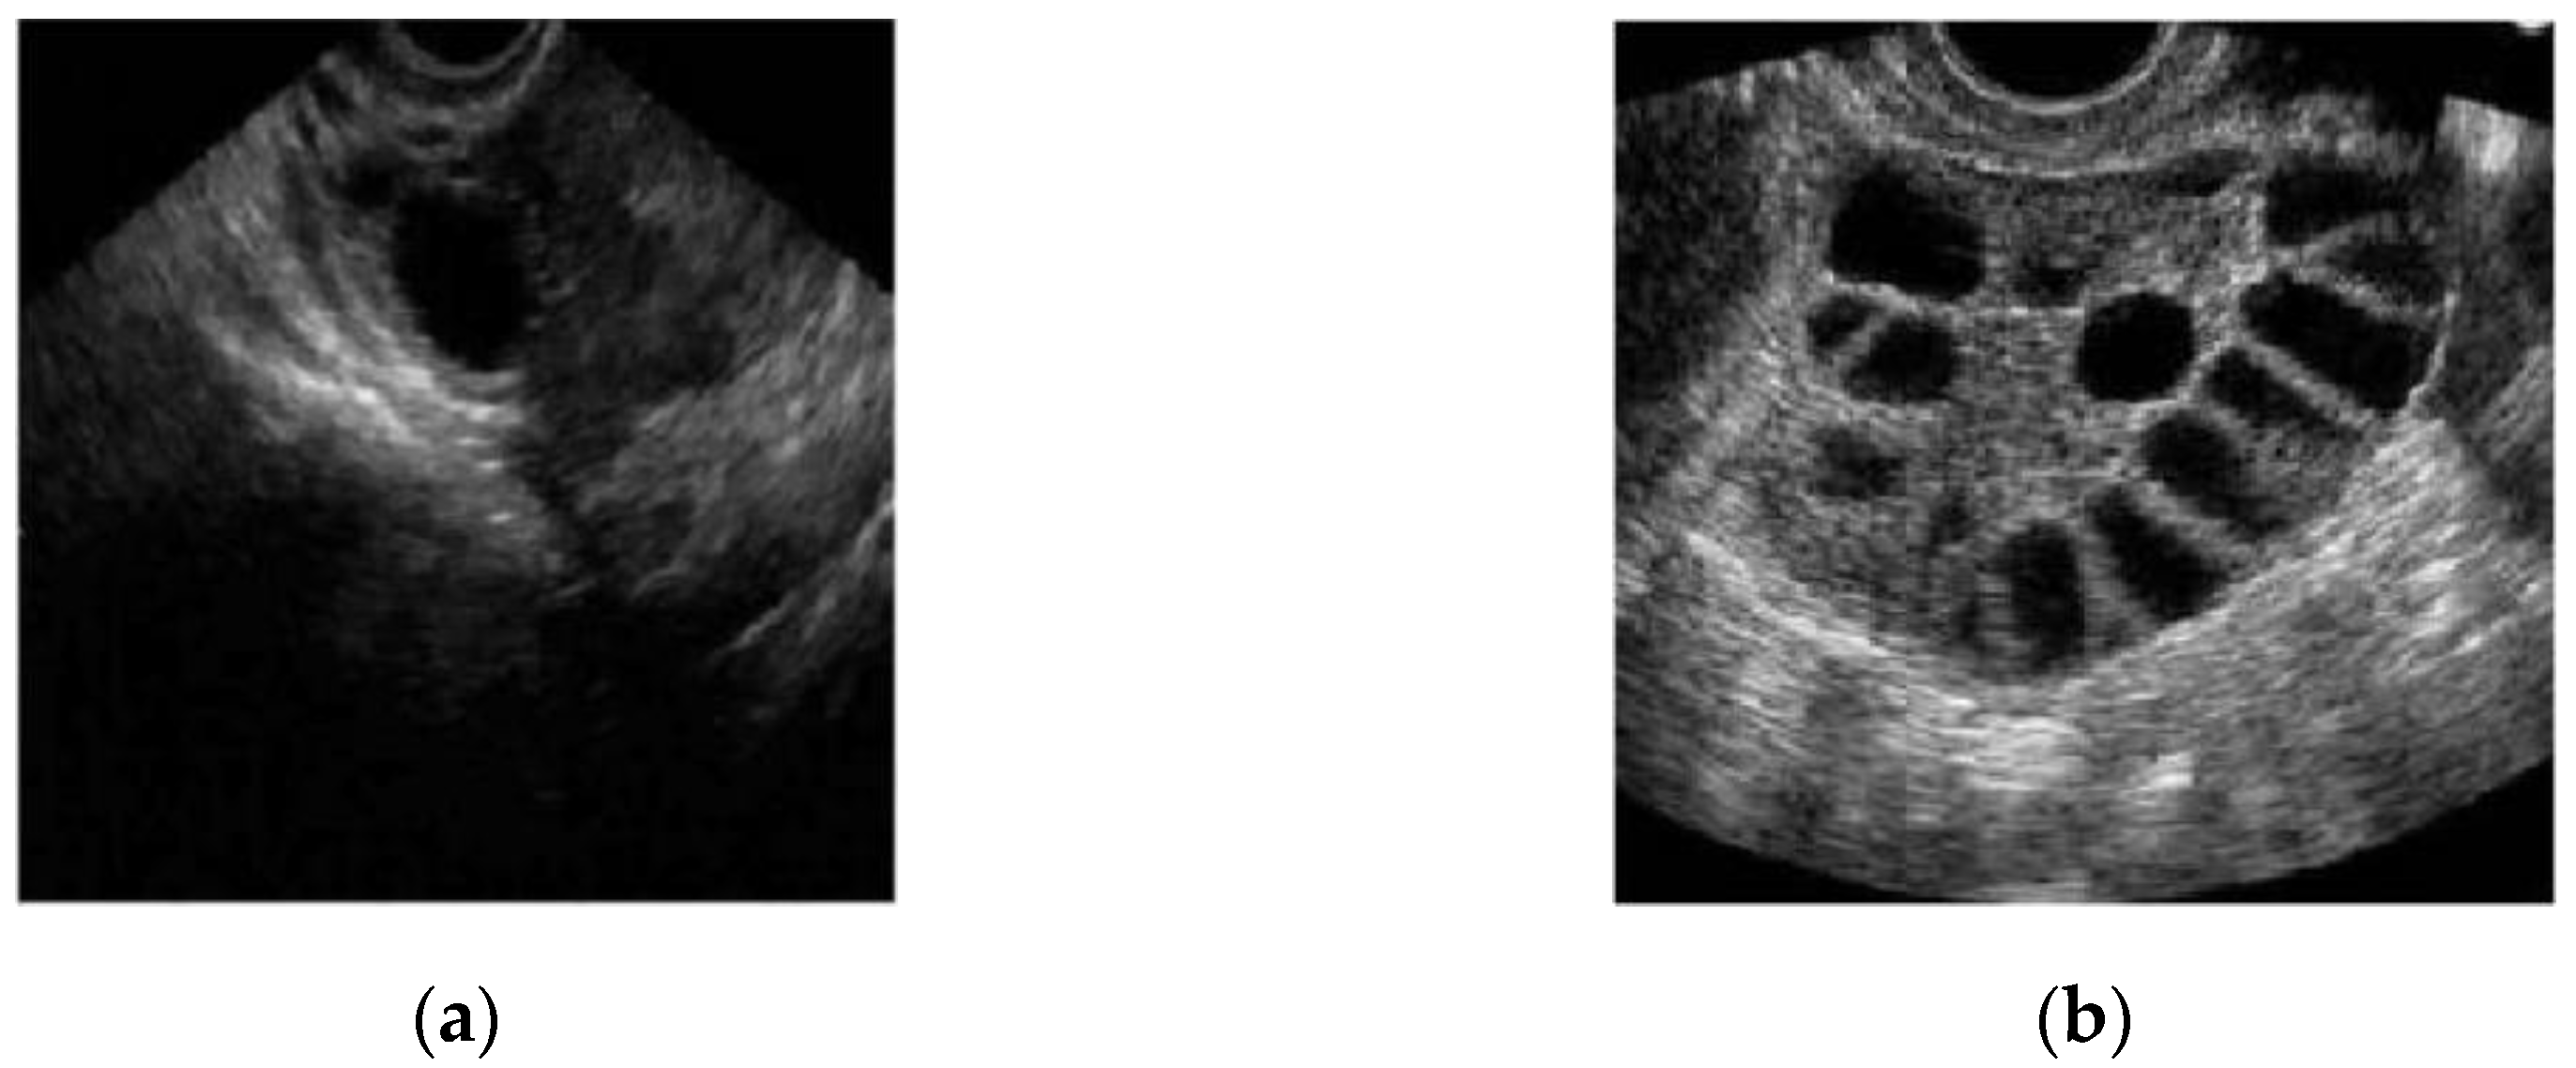

In conventional PCOS diagnosis, medical practitioners freeze-frame the ultrasound image in a satisfactory position and measure the follicle size. The size and number of follicles can be measured manually or by marking the measurement to determine whether the follicles show PCOS characteristics. These steps are repeated for each follicle [16]. Figure 2a,b show two different ultrasound images of normal and polycystic ovaries [17].

Figure 2.

Ultrasound image of (a) a normal and (b) a polycystic ovary [17].